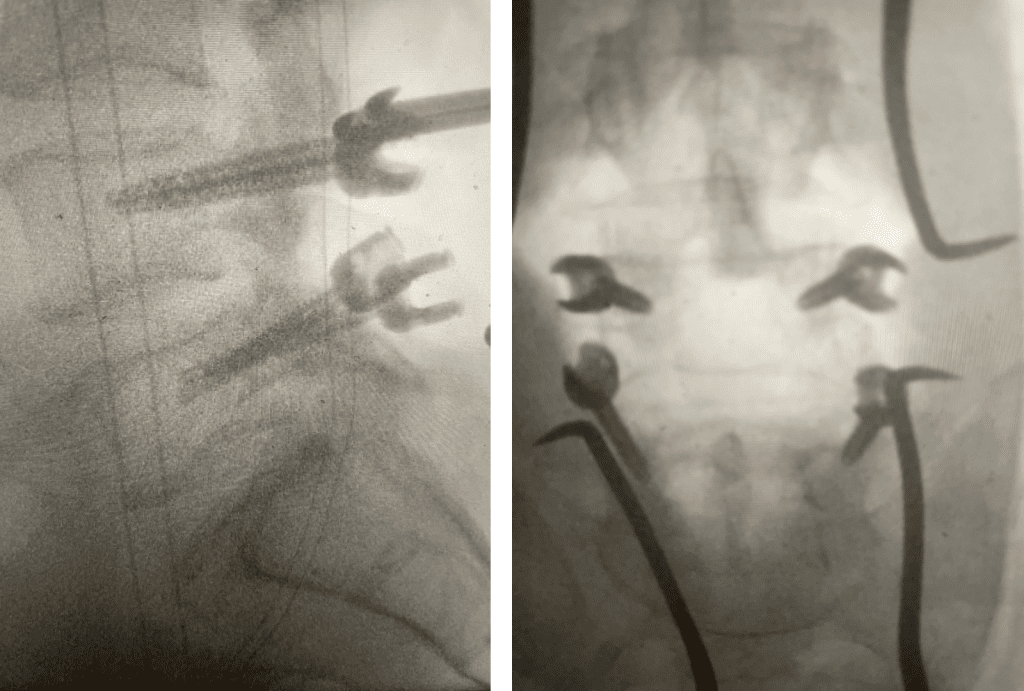

Fig 2: Intraoperative photo showing the thecal sac (arrow)completely decompressed after L3-5 laminectomy. Note the L5 nerve root very well decompressed (asterix)

During the surgery we perform what is called a decompressive laminectomy. Because he had the slip at L4-5 he required a fusion in addition. We elected to use screws with bone graft. People wonder what an actual laminectomy is. A laminectomy is a procedure to remove or “ectomy” the back ring of bone of the spinal segment .You literally bite it away with our special instruments. This bone is called the lamina. You do not need the lamina to live, like an appendix. There are gaps between each lamina segment going up the spine to begin with and there is a tremendous amount of tissue including muscle so one is protected, and it is ok to do this. You need to do the laminectomy to shave away the material that is both hard and soft that is compressing the sac of nerves. Your goal in the surgery is to make the sac nice and round again with a normal diameter. Since in the lumbar spine there is no spinal cord you are dealing with the peripheral nervous system not the central nervous system like the brain and spinal cord. A sac of nerves floating in fluid is a protected system, like a baby in amniotic fluid. At the same time you must not only remove the pressure on the sac, but also you must shave away the pressure on the nerve roots as well, which is called a foraminotomy (Fig 2). The nice thing about a fusion is you can be aggressive in the amount of decompression and joint removal you can do because you are fixing chronic as well as iatrogenic acute instability.